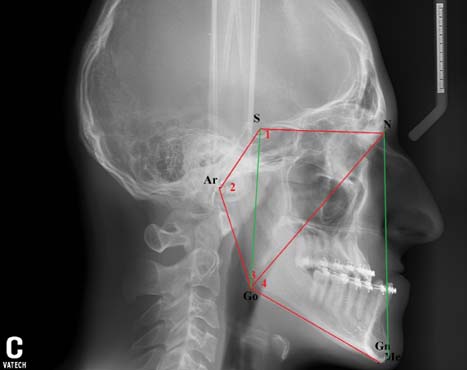

Наиболее убедительным из известных методов нам показался способ прогнозирования роста костей лицевого скелета по Т.Ф. Косыревой. В соответствии с рекомендациями автора [10] нанесли на ТРГ головы пациента К.В. антропометрические точки, провели линии (рис. 4).

Рис. 4. Прогнозирование направления роста лицевого скелета на профильной телерентгенограмме головы пациента К. по методу Т.Ф. Косыревой

NSL — плоскость основания черепа (по McLaughlin) от точки N до точки S.

FH — франкфуртская горизонталь (по Schwarz) через точки Or и Po.

NL — плоскость верхней челюсти (по McLaughlin) через точки ANS и PNS.

ML — плоскость тела нижней челюсти (по McLaughlin) через точки Me и Go.

Ось Y — (по Downs) от точки S до точки Gn.

B-Pg — линия (по Ricketts) от наиболее глубокой точки B в переднем отделе нижней челюсти (Downs) до наиболее передней точки подбородка Pg.

Далее определили значения углов.

∠NL-NSL (6,5°) — угол наклона основания верхней челюсти NL к основанию черепа NSL (отражает степень вертикальной ротации верхней челюсти).

∠NL-ML (22,0°) — базальный угол между плоскостью основания верхней челюсти NL и плоскостью тела нижней челюсти ML (отражает зубоальвеолярное развитие челюстей по вертикали).

∠BPg-ML (52,4°) — угол наклона линии подбородка по отношению к плоскости тела нижней челюсти (отражает степень развития нижней челюсти в переднем отделе).

∠YFH (57,0°) — нижний передний угол между осью Y и франкфуртской горизонталью FH (отражает переднезадний наклон оси лицевого отдела черепа).

∠ML-NSL (28,0°) — угол наклона плоскости ML к плоскости NSL (отражает степень и направление ротации нижней челюсти).

Полученные значения внесли в формулу по Т.Ф. Косыревой, расчёты по которой, по мнению автора, указывают на тип роста лицевого скелета:

Выполненные нами расчёты дали следующий результат:

Полученное значение (1,22) указало на вертикальный тип роста костей лицевого скелета, что соответствовало другим результатам нашего исследования профильных ТРГ головы пациента К. (табл. 3).